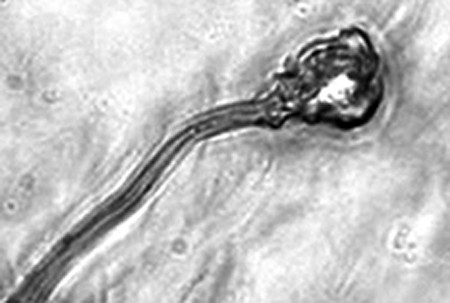

據(jù)報(bào)告的主要作者卡里姆教授介紹,這種試管培育精子(IVDsperm)與人類自然產(chǎn)生的精子并不完全一樣,但兩者擁有4個(gè)重要的相似點(diǎn):它們包含有23個(gè)染色體;有精子那樣的頭和尾巴;有可以使卵細(xì)胞受精的蛋白質(zhì);它們也可以像天然精子一樣游動(dòng)。